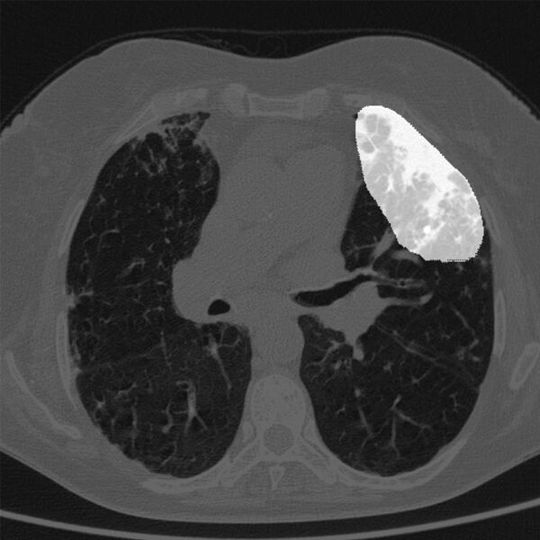

Das System von NTT Data und DeepTek erkennt unter anderem Anomalien in medizinischen Aufnahmen.(Bild:  NTT Data)

Das System von NTT Data und DeepTek erkennt unter anderem Anomalien in medizinischen Aufnahmen.

NTT Data will unter anderem dem weltweiten Mangel an Radiologen begegnen. Speziell im Kontext mit COVID-19 steigt laut dem Unternehmen die Bedeutung bildgebender Verfahren, um mögliche Lungenentzündungen zuverlässig zu diagnostizieren. Das KI-Verfahren von NTT Data vergleicht Aufnahmen mit den Bildern gesunder Personen, zeigt mögliche Anomalien auf und liefert Beschreibungen in Textform.